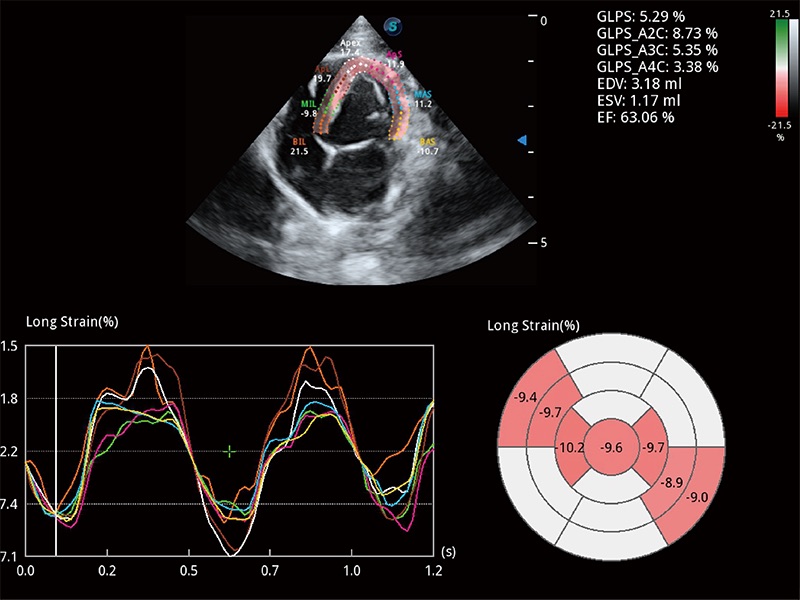

通过心肌识别技术与二维斑点追踪技术相结合,对心脏的超声图像进行量化分析。计算心肌17个节段的应变、应变率、速度、位移等,并通过牛眼图的形式进行呈现。

能够基于左心室壁追踪和辛普森法,自动计算射血分数,支持多个可移动点描迹,与手动测量相比,极大节省了动物医生的时间和精力。

实时用颜色表示心肌组织运动,观察和定量组织的运动情況,对快速检测与评估心肌的灌注和活性、电传导及心肌收缩和舒张功能等均能提供重要的诊断信息。